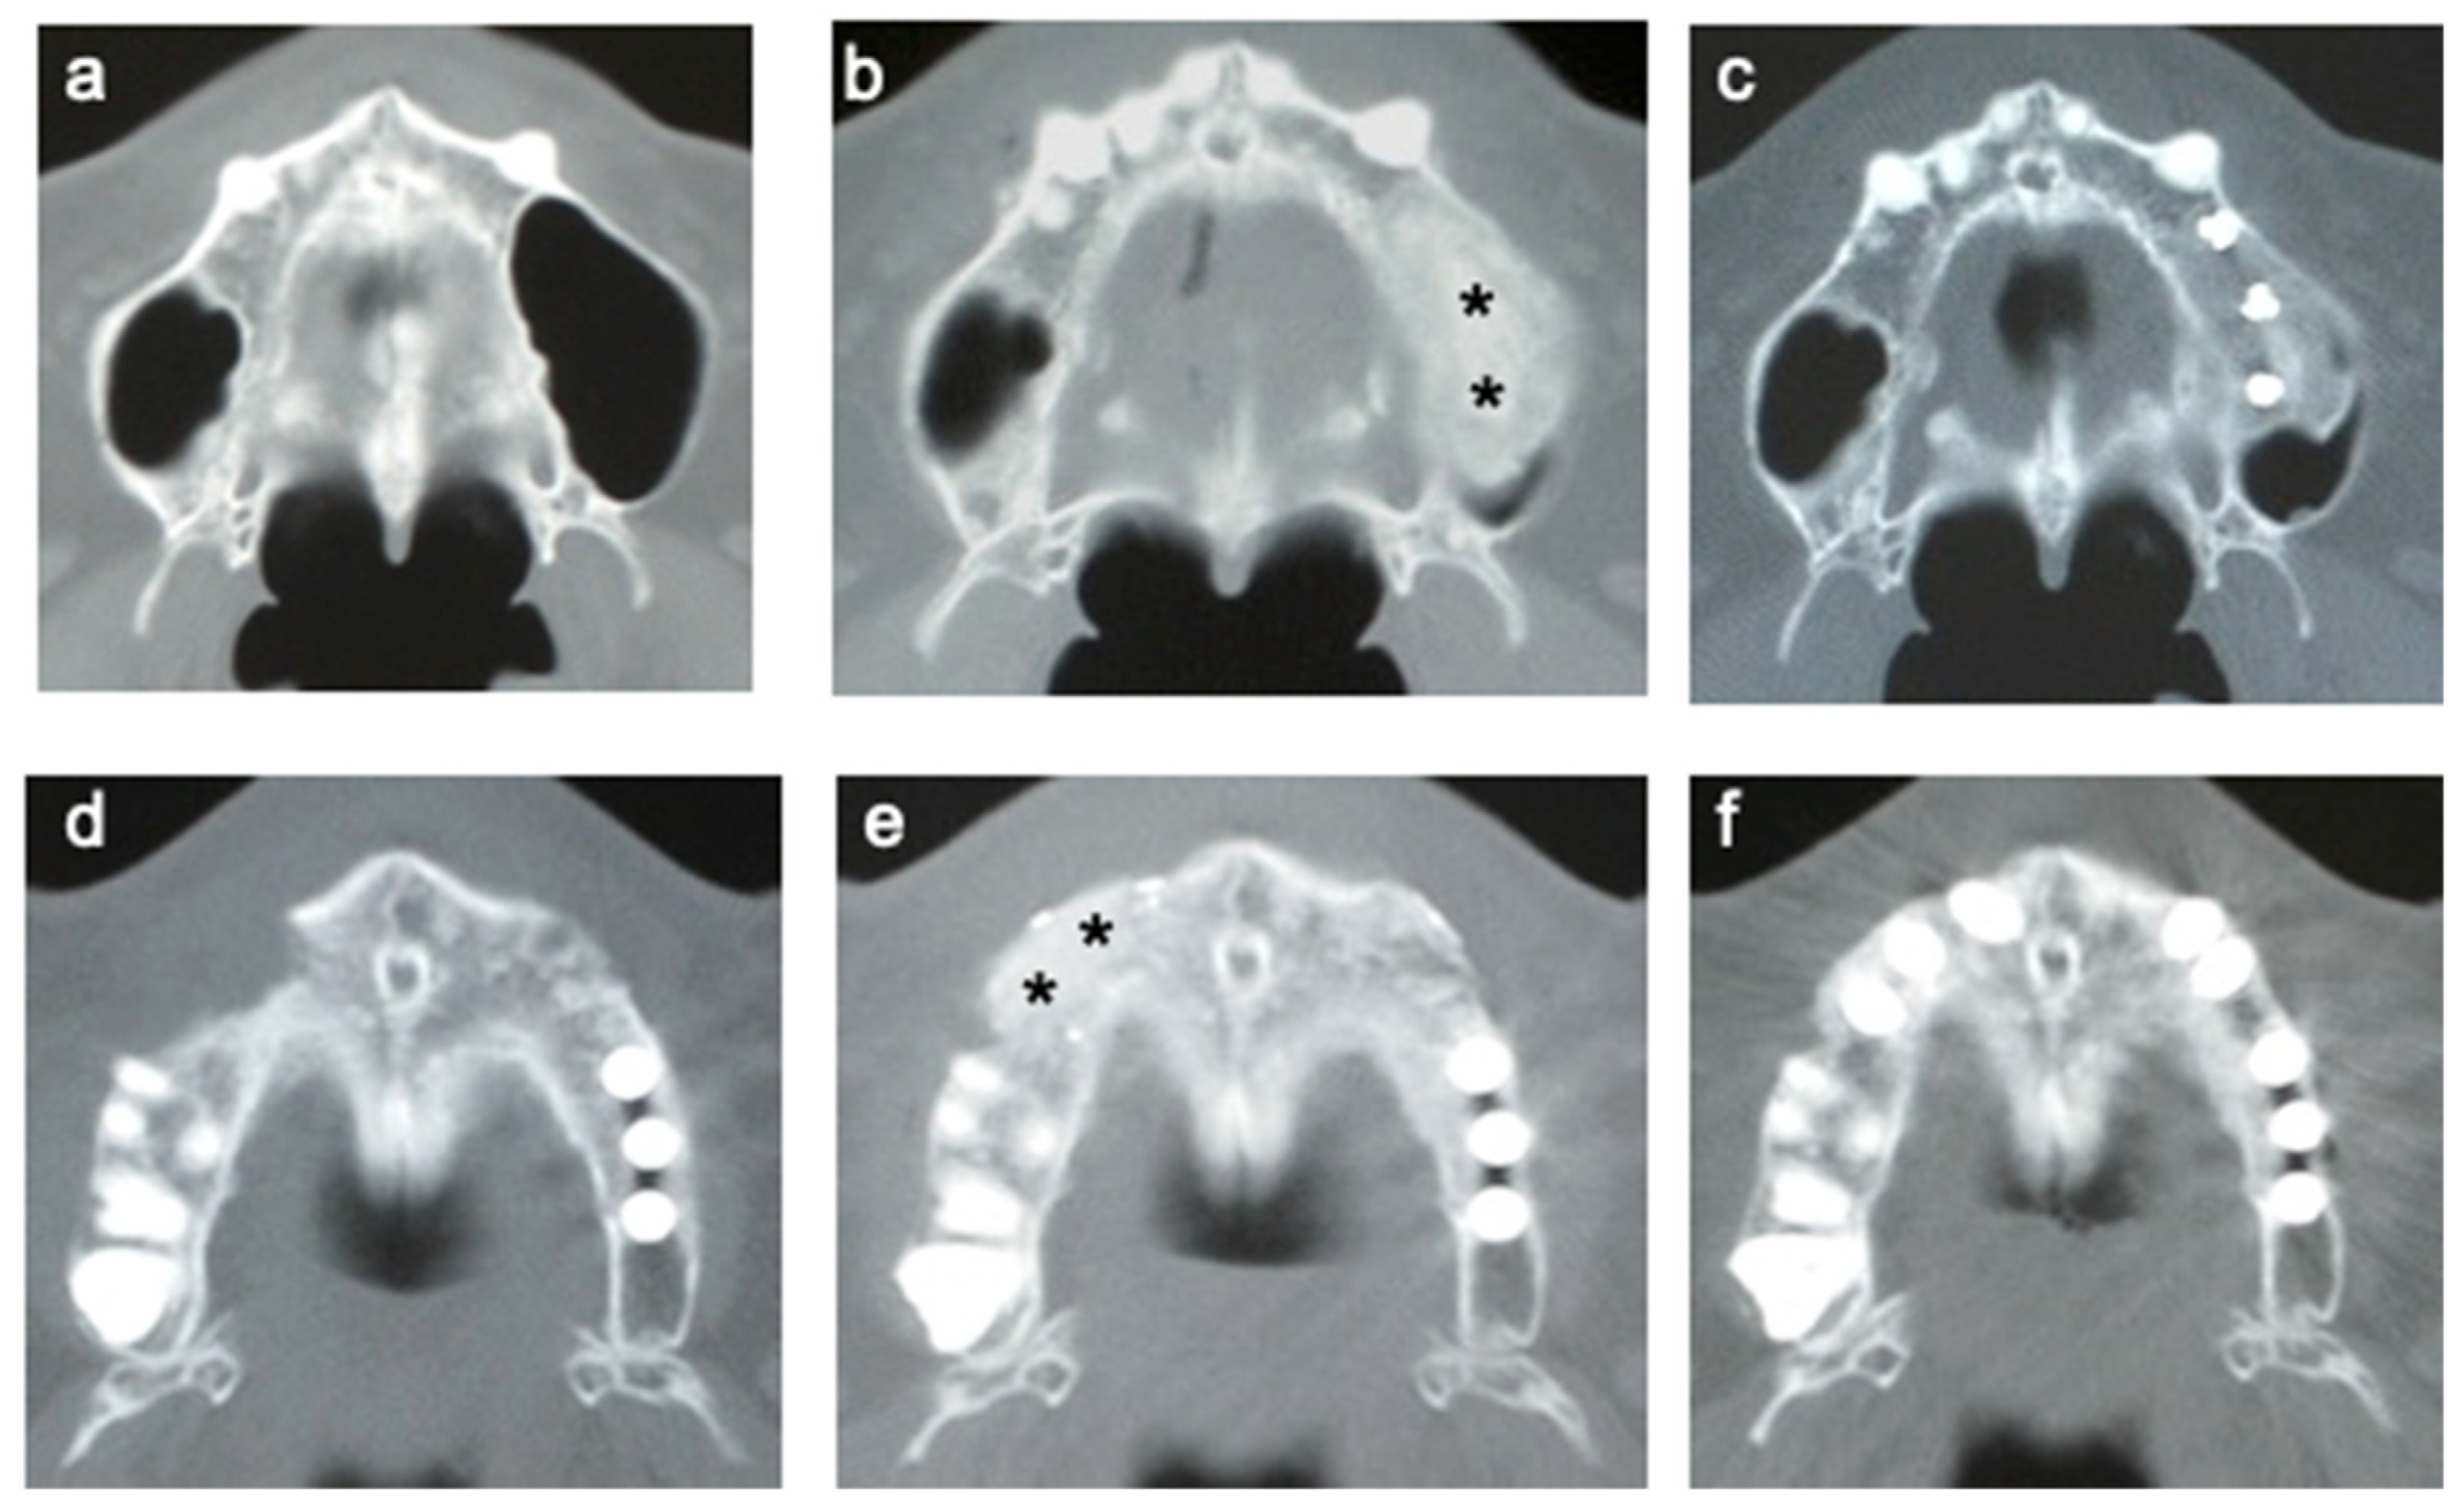

3.5. CT of Alveolar Bone

3.6. Time Course of the Volume of Regenerated Bone